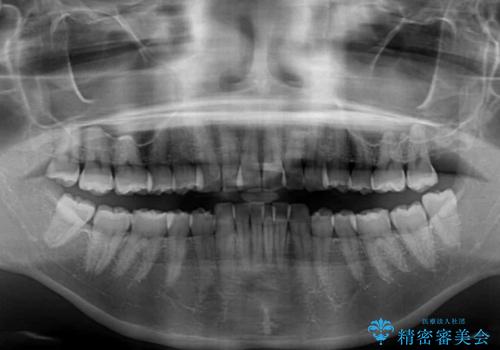

- 前方に主張した前歯2本を気にして来院された患者様です。

下顎前歯がデコボコしており、その影響で上顎前歯が前方に押し出されている状態でした。

口元が閉じにくいという印象はなかったため、非抜歯矯正にて歯列を整えていくこととしました。

上下左右の親知らずを抜歯し、上下ともに歯列を後方と側方に拡大し、口元を突出させることなくデコボコを解消することとしました。